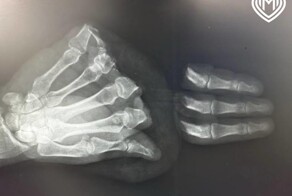

- Врачи помогли мужчине, который отрезал себе 4 пальца циркулярной пилой

- Травма на производстве. Врачи пришили сразу 5 пальцев во время одной операции